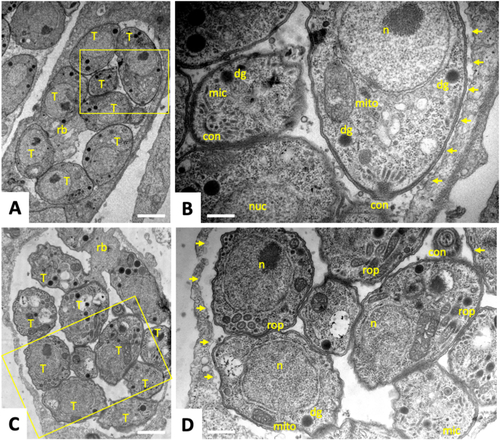

Transmission Electron Microscopy of T. gondii tachyzoites grown in human foreskin fibroblasts. Cells were fixed at 48 h (A, B) and 72 h (C, D) post-infection. Boxed areas in A and C are enlarged in B and D, respectively. T = tachyzoites, n = nucleus, con = conoid, mic = micronemes, rop = rhoptries, dg = dense granules, mito = mitochondrion, rb = residual body; small arrows point towards the parasitophorous vacuole membrane. Bars in (A) = 1.4 μm; (B) = 0.4 μm, (C) = 1.4 μm; (D) = 0.6 μm.